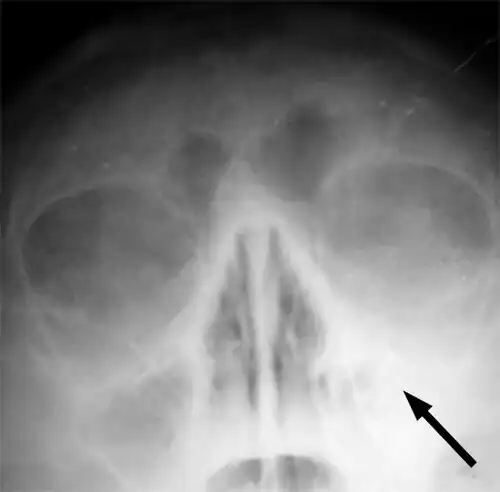

Imaging by either X-ray, CT, or MRI is generally not recommended unless complications develop.[66] Pain caused by sinusitis is sometimes confused for pain caused by pulpitis (toothache) of the maxillary teeth, and vice versa. Classically, the increased pain when tilting the head forwards separates sinusitis from pulpitis.[68]

For cases of maxillary sinusitis, limited field CBCT imaging, as compared to periapical radiographs, improves the ability to detect the teeth as the sources for sinusitis. A coronal CT picture may also be useful.[60]

For sinusitis lasting more than 12 weeks, a CT scan is recommended.[66] On a CT scan, acute sinus secretions have a radiodensity of 10 to 25 Hounsfield units (HU). In a more chronic state, they become more viscous, with a radiodensity of 30 to 60 HU.[69]